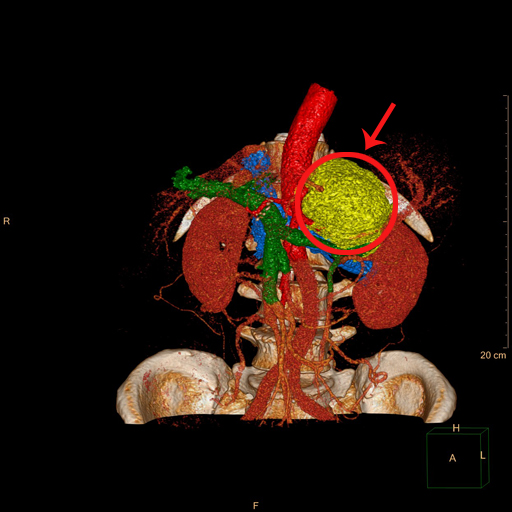

近期,家住内蒙古锡林郭勒的刘先生时感胸口憋闷,伴有头晕症状,在当地医院就诊怀疑是心脏病,经介绍来到首都医科大学附属北京潞河医院泌尿外科就医。刘先生住院后进行了必要检查,经心脏彩超检查并未发现有严重的问题,反而是腹部CT检查发现其左侧肾上腺有肿瘤,最大径12cm。泌尿外科副主任贤少忠随后为刘先生做了血液相关化验检查,发现刘先生的血儿茶酚胺较正常值升高了40倍,贤少忠确定这是一个少见的巨大嗜铬细胞瘤,肿瘤与肾脏、脾脏的血管以及腹腔干紧密粘连,并且病人的嗜铬细胞瘤分泌功能旺盛,会导致血压过山车式的剧烈波动,因此手术风险极大。细心的贤少忠发现,病人的左肾还有一个不起眼的小肿瘤,并且病人的前列腺特异抗原(PSA)是正常值的3倍,这意味着病人可能同时存在肾上腺嗜铬细胞瘤、肾肿瘤、前列腺癌三种肿瘤,这使本来棘手的问题变得更加复杂。

在进行了充分的扩血管、扩容及肠道清洁等准备后,第一阶段进行了腹腔镜下左肾上腺肿瘤切除+左肾肿瘤剜除+经会阴前列腺穿刺活检手术。手术由贤少忠主刀完成,为避免挤压肾上腺瘤体造成血压剧烈波动,他采用了对瘤体扰动最小的经腹入路,迅速暴露肾上腺中央静脉并结扎,切断了激素的入血之路,使后面的手术过程更加平稳。然后他小心翼翼地围绕肿瘤抽丝剥茧,成功地将这枚巨型炸弹完整拆除。由于肾肿瘤位于肾上极的背侧,贤少忠在患者腋后线增加1枚辅助Trocar改行经腰入路,仅用时8分钟便完成了左肾肿瘤剜除手术,将热缺血时间压缩到远低于国际安全阈值(25分钟)。最后,采取超声引导下经会阴前列腺穿刺活检手术。幸运的是术后病理证实左刘先生的肾肿瘤为良性的血管平滑肌脂肪瘤,不幸的是前列腺靶向穿刺1针为恶性。